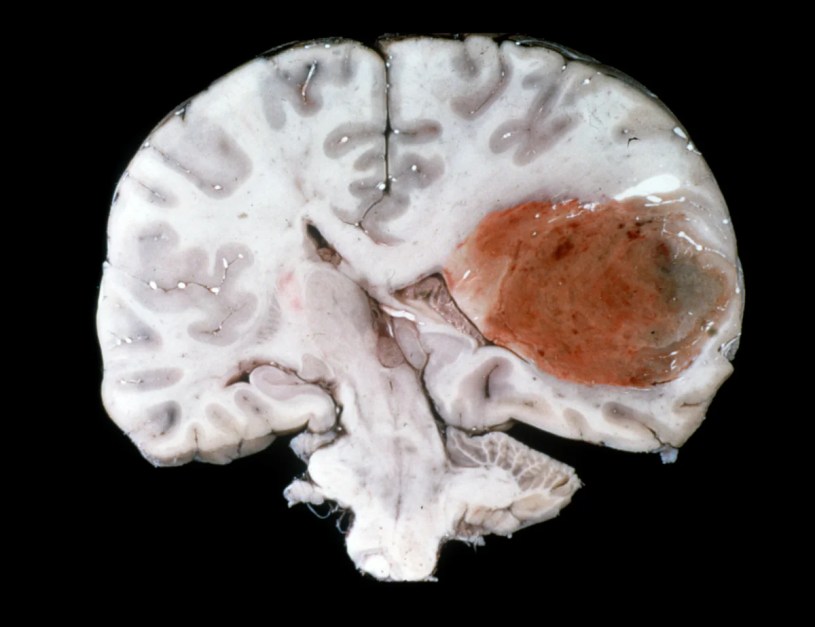

Il glioblastoma o astrocitoma di grado IV è il più aggressivo tumore cerebrale primario. Colpisce soprattutto il cervello, ma può insorgere anche in tronco encefalico, cervelletto e midollo spinale, rappresentando il 45 per cento dei tumori cerebrali primitivi. Origina dalle cellule gliali di supporto ai neuroni, ma può derivare anche da cellule progenitrici simili a staminali neurali. L’incidenza è di 3-4 casi ogni 100mila abitanti l’anno, con maggiore frequenza tra 45 e 75 anni, negli uomini e nei caucasici.